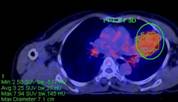

Ca lâm sàng 2: Bệnh nhân Nguyễn T.V., nữ, 72 tuổi. Chẩn đoán: U lympho ác tính không Hodgkin biểu hiện tại phổi, GPB: WF6. Hình CT và PET/CT cho thấy khối u phổi trái tăng hấp thu FDG (vòng tròn) với max SUV=7,94.